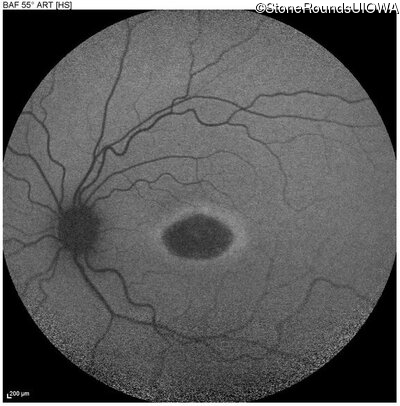

This 22 year old man had macular abnormalities noted incidentally at a routine eye exam at age 19. Since then, he has experienced a gradual loss of acuity particularly in the left eye.